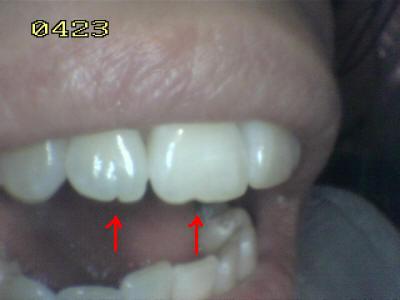

En apariencia una relación

canina normal (guía anterior)

Observe el desgaste del canino inferior,

que no cumple la función de guía canina, y la función de

grupo posterior de premolares y hasta del primer molar. |

Por falta de guía canina en el lado de

trabajo, hay un desgaste de los bordes incisales del lateral

y central |